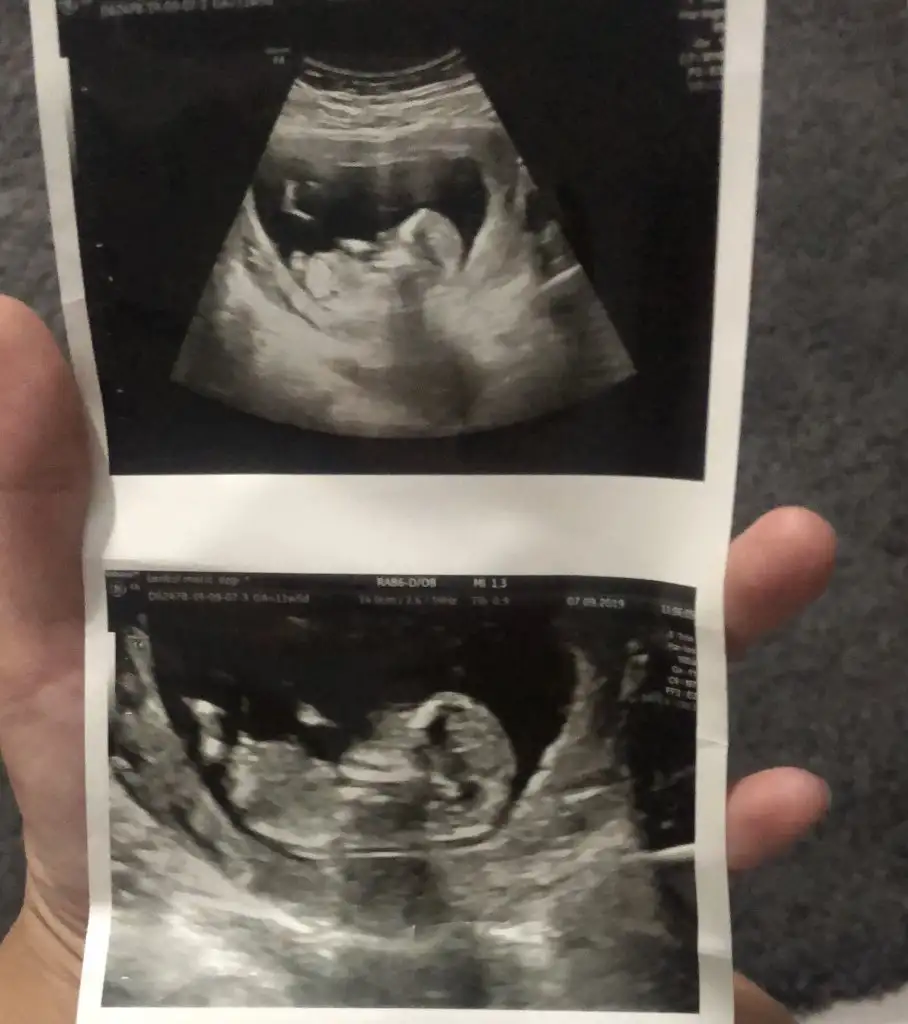

KızEki Görüntüle 2307183 Eki Görüntüle 2307184 kizlar 1. 10 haftalik 2. 12+4 lutfen banada yorum yapin sizce ne